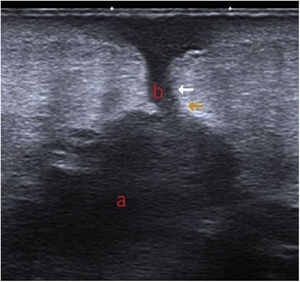

Exploraciones complementariasEn la imagen ecográfica se observaba, por debajo del tejido celular subcutáneo, un área hipoecoica de bordes irregulares y de morfología polilobulada (a) que se comunicaba con la superficie cutánea a través de un trayecto lineal hipoecoico (b) (fig. 3). Mediante la gammagrafía con leucocitos marcados se apreciaban depósitos leucocitarios focales y progresivos localizados en la periferia del material protésico del hombro derecho, sobre todo en su región proximal.